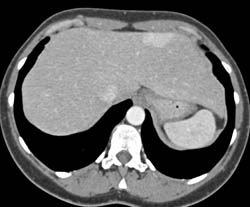

Focal Nodular Hyperplasia (FNH)